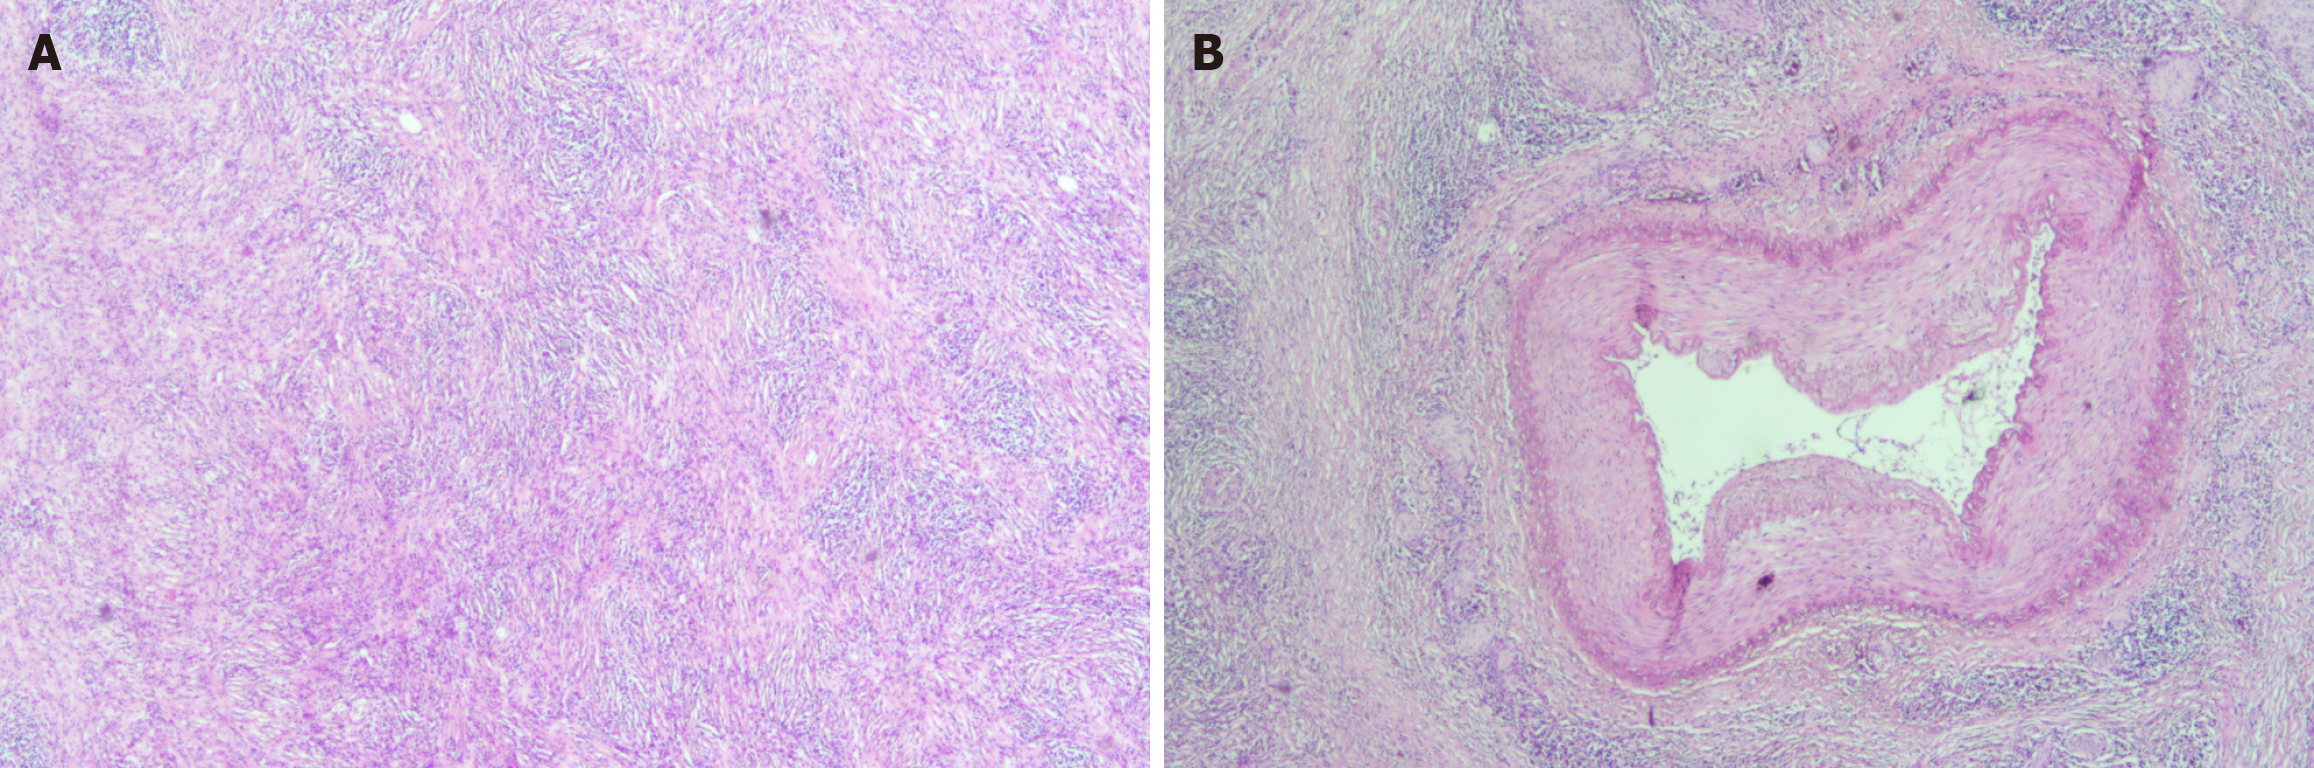

The patient was diagnosed with IRPF (Figure 2A and B) that invaded the muscularis propria of the colon following surgery.